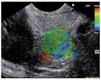

Representative areas from the mass (A) and soft reference areas (B) are analyzed. The result of the elastographic evaluation is defined by the quotient B/A (strain ratio). In Figure 6 a ratio-elastography of a pancreatic cancer is shown (ratio=25.27).

Figure 6. A ratio-elastography is shown. The ratio between measures in the small circle of normal tissue (A) and cancer tissue in the big circle (B) is over 10 (ratio=25.27).